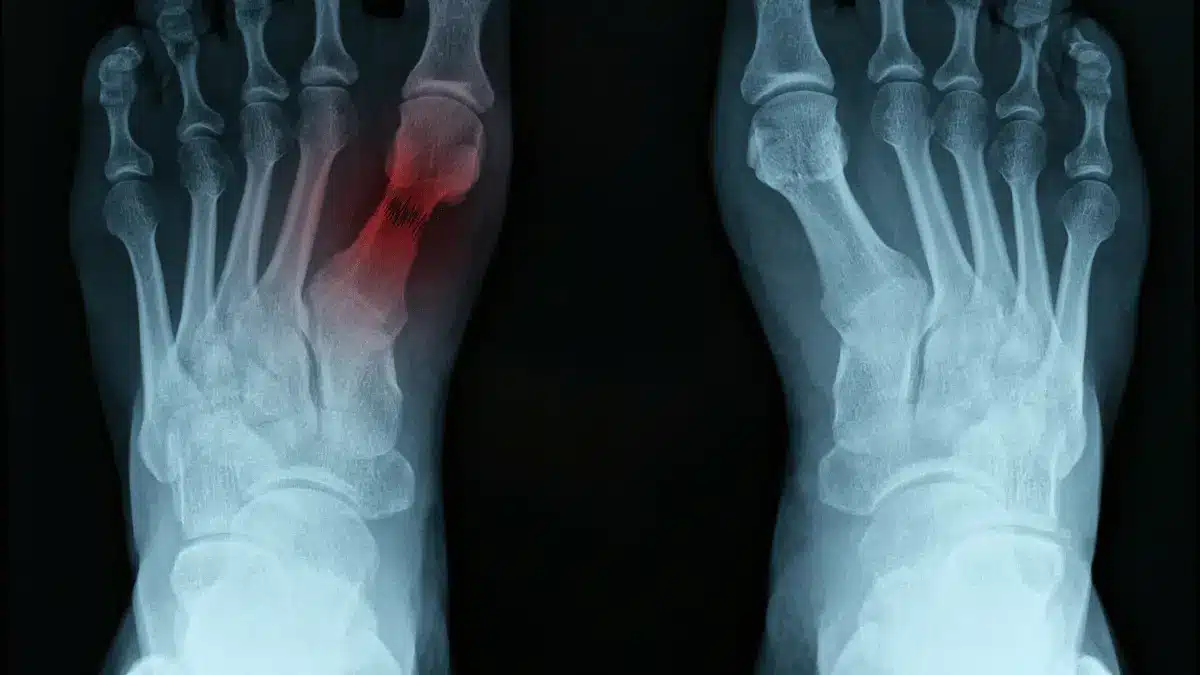

Doença de Freiberg: sintomas, diagnóstico e tratamento

A doença de Freiberg é uma causa de dor no antepé, geralmente na região do segundo dedo. Ela acontece quando…